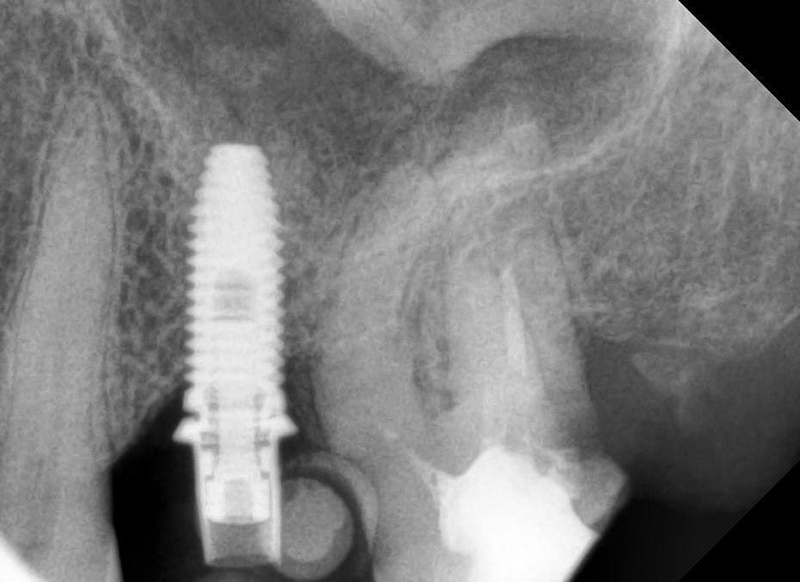

Последовательные снимки перелечивания корневых каналов седьмого с выявленным дефектом задней поверхности корня

Кажется, здесь судьба решила над нами сжалиться, и всё прошло хорошо. Это был длинный ряд факапов, где вмешивалась куча разных факторов — и особенности строения челюсти пациента, и коронавирус, и появившееся от всего происходящего недоверие к врачам. Выровнять ситуацию в таких случаях удаётся последовательными правильными действиями. Нужно, чтобы совпала техническая оснащённость и медицинские скилы, чтобы в конце концов прийти к объективно хорошему клиническому результату и восстановлению взаимопонимания с пациентом.

Установленные временные коронки. Объект на шестом зубе легко принять за кариес, но на самом деле это шахта винта, который держит временную коронку на импланте. В общем, зуб выглядит сейчас страшненько, но это живое фото в процессе лечения. Новых фото, где он уже совсем здоровый и красивый, пока ещё нет. Кстати, если бы кариес на этом зубе был, то есть когда у нас не тотальная реставрация зубов, а какие-то небольшие полости, мы бы лечение не задваивали, а устраняли бы дефекты уже во время финальной реставрации. При тотальной реставрации мы бы всё зачистили заранее.